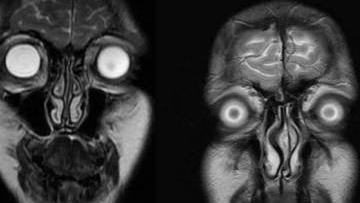

Вредно ли МРТ для здоровья

Есть ли вред от МРТ - этот вопрос может возникнуть у пациента, когда ему рекомендуют сделать магнитно-резонансную томографию. Если вы получили направление на МРТ, это не означает, что у вас есть какое-то заболевание...

МРТ наверное один из самых широко освещаемых методов диагностики в современной медицине. Во многих источниках, начиная от рекламных буклетов клиник и заканчивая некоторыми учебниками для студентов медиков. Подчёркиваются преимущества МРТ, такие, как высокая информативность диагностики различных заболеваний, и отсутствие лучевой нагрузки. МРТ высокоточный и безопасный метод обследования, гласят информационные таблоиды. Так ли это на самом деле? Если обратиться к официальным источникам, то скорее да, хотя и там все не так однозначно...